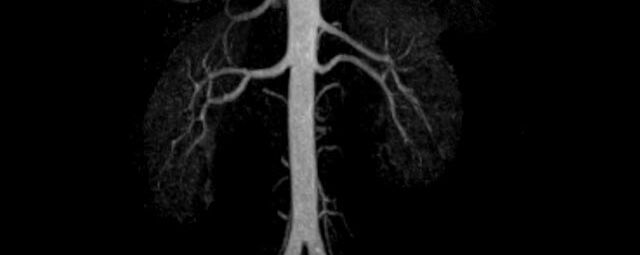

• Bauchgefäße

• Erfassung und Verlaufskontrolle bei arteriellen Aneurysmen (Aussackungen der Arterien), vor allem der Bauchaorta

• Darstellung von Gefäßengen an Nierenarterien, Baucharterien und Becken-/Beinarterien

MR-Angiografie (MRA)

• MR-Angiografie ohne Kontrastmittel

• Time of Flight (TOF)-Angiographie

Je nach Fragestellung und Körperregion Gefäßdarstellung ohne Kontrastmittel bei Kontrastmittelunverträglichkeit oder terminaler Niereninsuffizienz möglich.

• MR-Angiographie mit Kontrastmittel

• Erfassung arterieller und venöser Gefäße/Bypässe aller Körperregionen mit 3D-Rekonstruktion